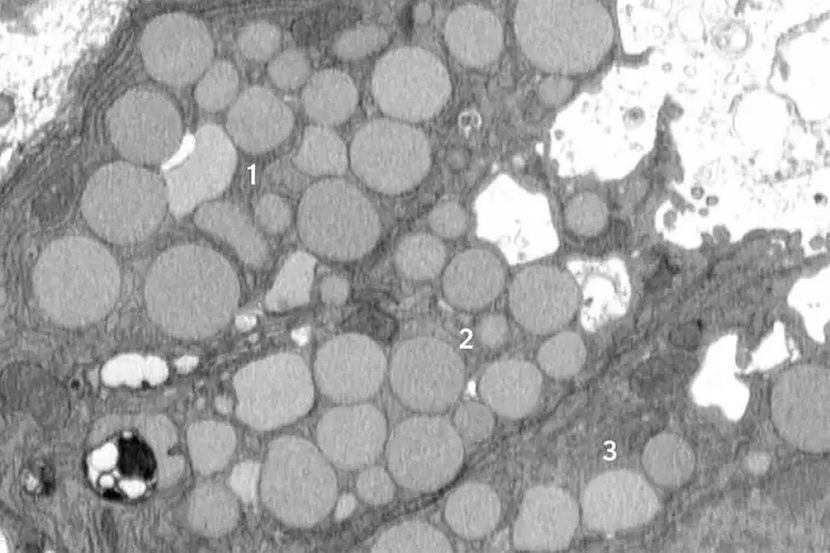

Katartocitoza je identifikovana u okviru značajnog regenerativnog odgovora na povredu zvanog paligenoza, kad povređene ćelije napuštaju svoje normalne uloge i prolaze kroz proces reprogramiranja do nezrelog stanja, ponašajući se kao brzo deleće matične ćelije, što se dešava tokom razvoja.

Prvobitno su istraživači pretpostavljali da se uklanjanje ćelijske mašinerije u cilju pripreme za reprogramiranje dešava potpuno unutar ćelijskih odeljaka zvanih lizozomi, gde se otpad razgrađuje u sporom i izdvojenom procesu.

Međutim, od početka su primetili otpatke izvan ćelija. Inicijalno su to zanemarili kao nevažno, ali su videli sve više eksternog otpada. Model želudačne povrede kod miševa koja je izazvala reprogramiranje zrelih ćelija u stanje matičnih ćelija, svih odjednom, pokazao je da je reakcija „povraćanja“ odlika paligenoze. Drugačije rečeno, proces povraćanja nije sporadičan, već novoidentifikovan, standardan način reagovanja ćelija na povredu.